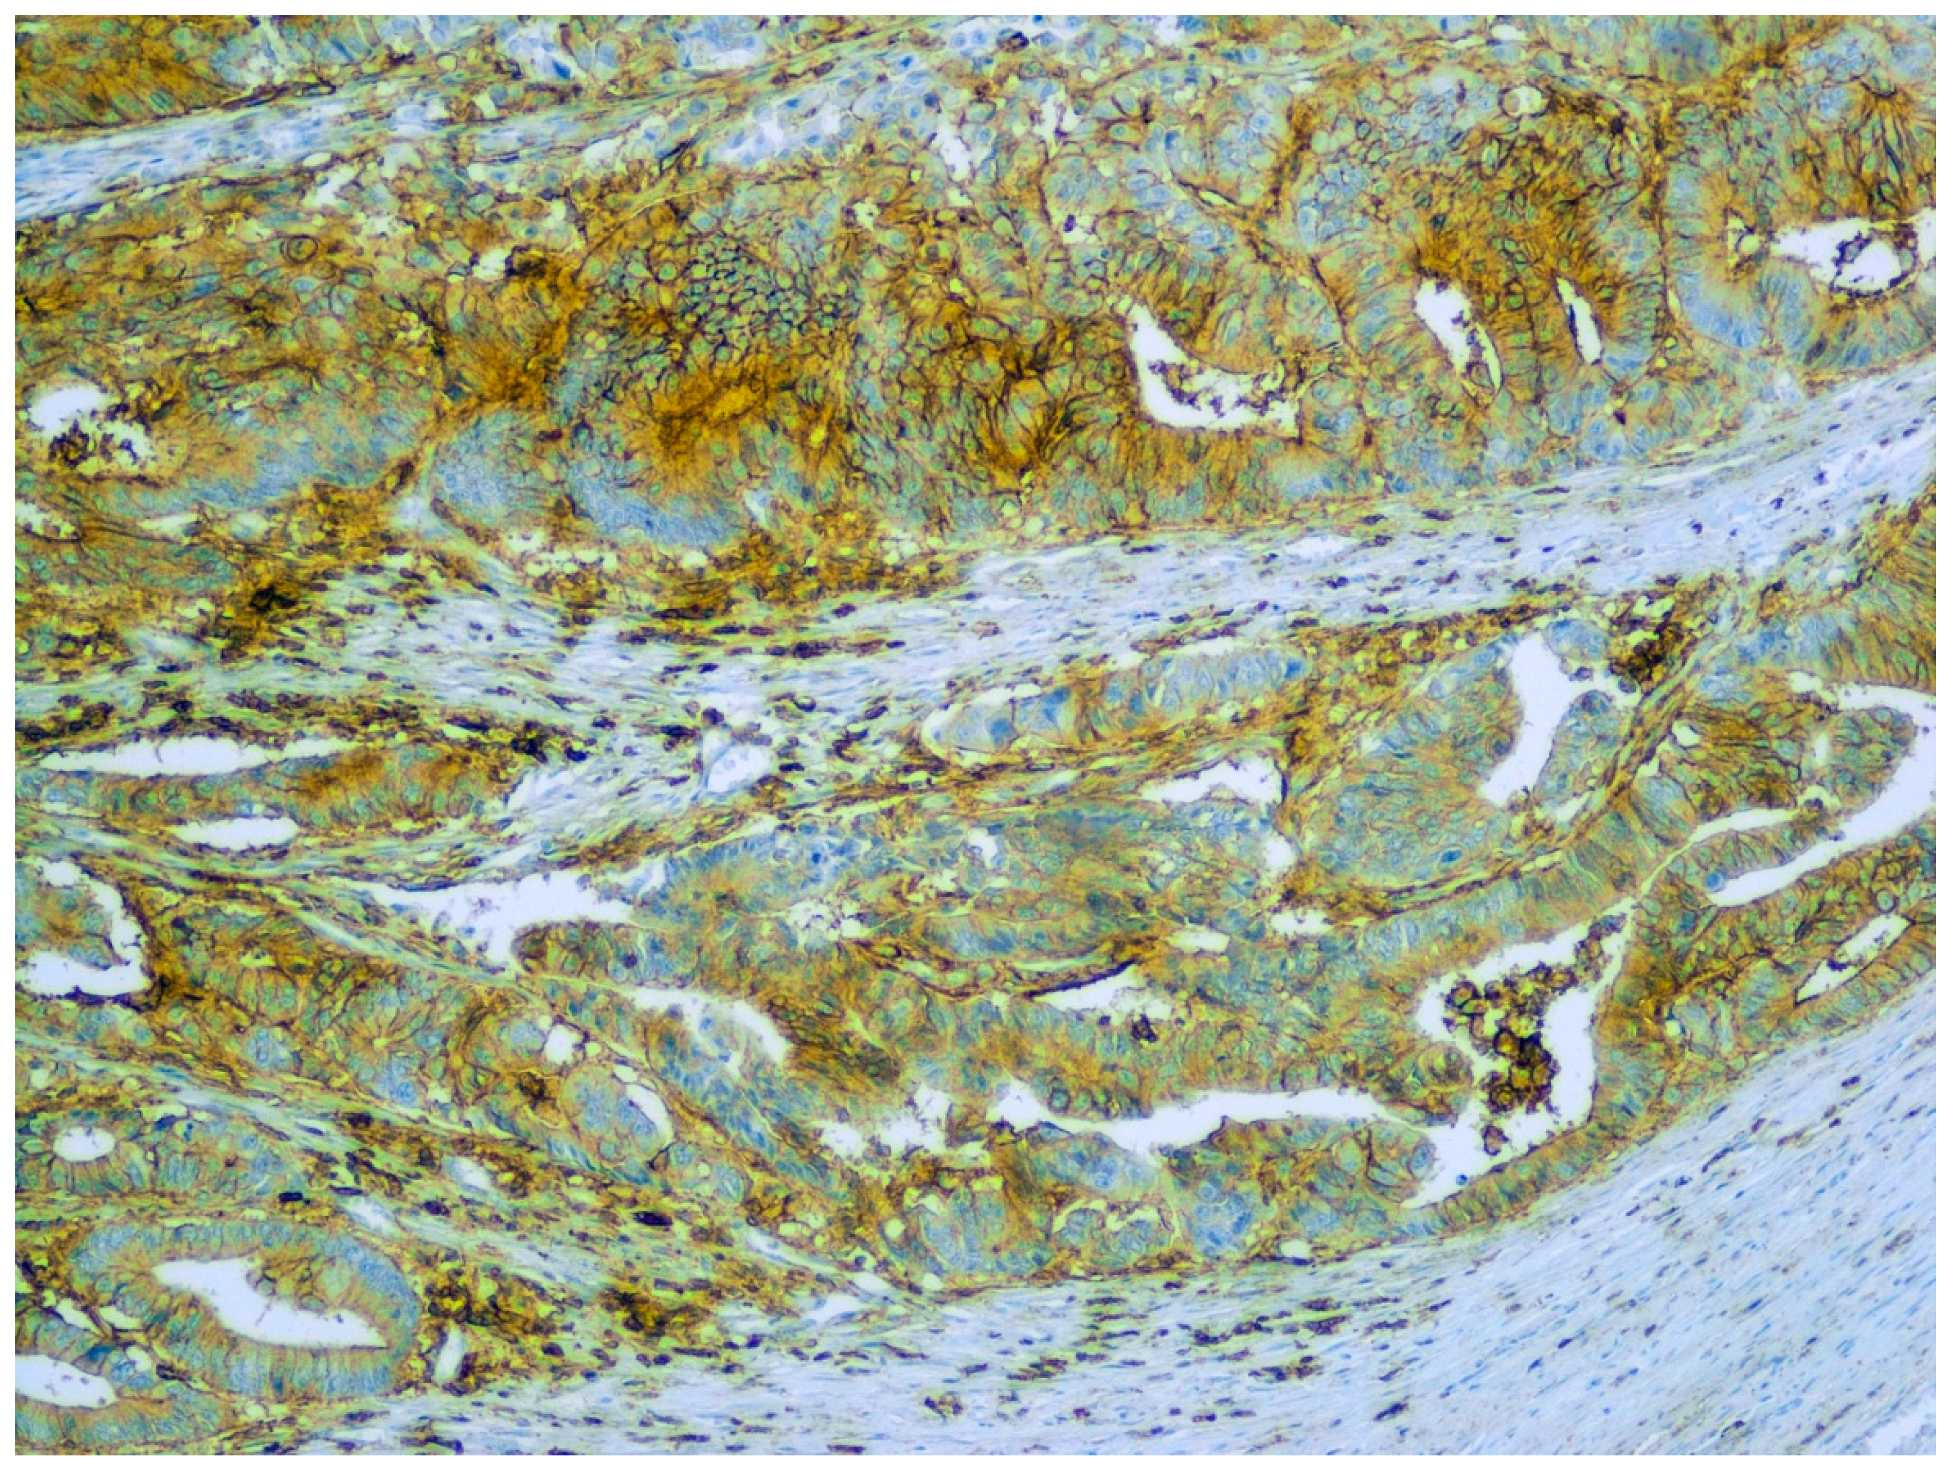

- Ilie, D.S.; Mitroi, G.; Păun, I.; Ţenea-Cojan, T.; Neamţu, C.; Totolici, B.D.; Sapalidis, K.; Mogoantă, S.; Murea, A. Pathological and immunohistochemical study of colon cancer. Evaluation of markers for colon cancer stem cells. Rom. J. Morphol. Embryol. 2021, 62, 117–124. [Google Scholar] [CrossRef]

- Briede, I.; Strumfa, I.; Vanags, A.; Gardovskis, J. The Association Between Inflammation, Epithelial Mesenchymal Transition and Stemness in Colorectal Carcinoma. J. Inflamm. Res. 2020, 8, 15–34. [Google Scholar] [CrossRef] [PubMed] [Green Version]